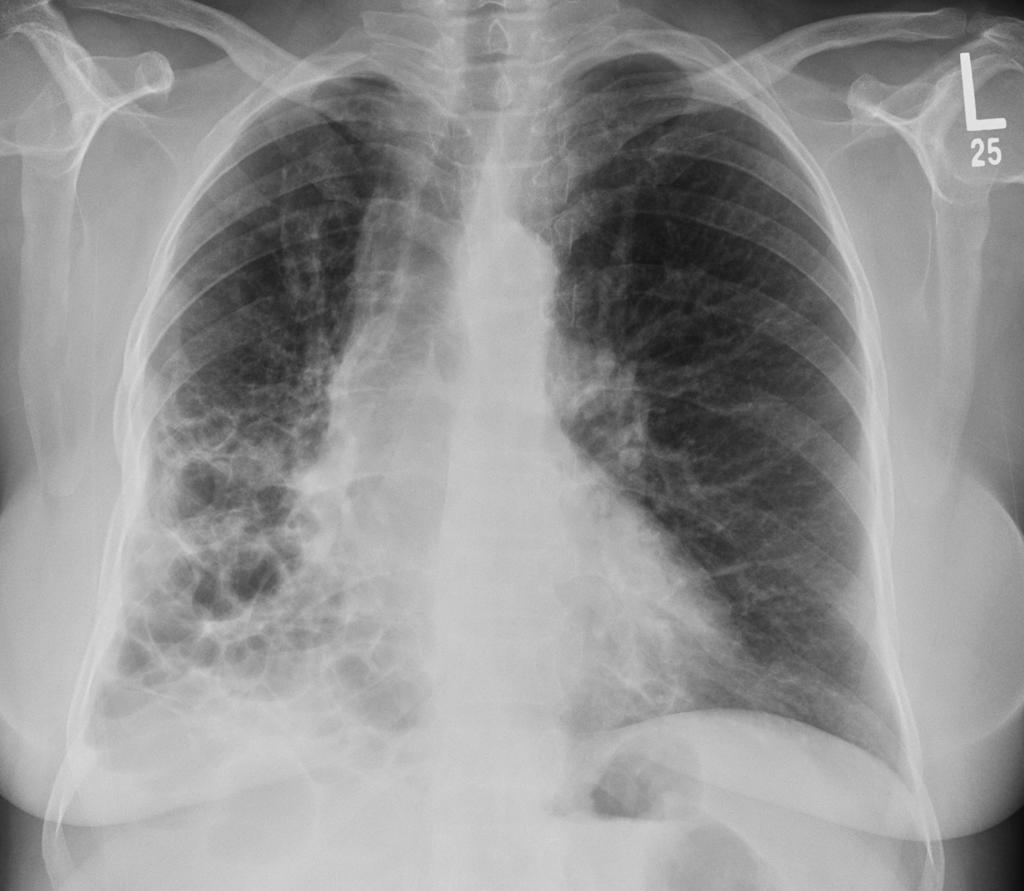

但间质性肺疾病让这个"工厂"出现了问题,肺泡壁变厚变硬,就像在氧气和血液之间加了一堵墙,气体交换效率大打折扣

美国肺脏协会的研究数据显示,间质性肺疾病患者的最大摄氧量比正常人减少40-60%

这意味着什么呢?简单说,就是别人爬三层楼不喘气,你可能爬一层楼就需要休息